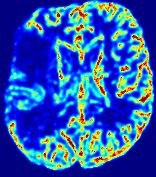

4.3.2 Diffusion Imaging via Advection-Diffusion

Slice #1Slice #2Slice #3Slice #4Slice #5Slice #6Dgtsuperscript𝐷gtD^{\text{gt}}Refer to captionRefer to captionRefer to captionRefer to captionRefer to captionRefer to captionDestsuperscript𝐷estD^{\text{est}}Refer to captionRefer to captionRefer to captionRefer to captionRefer to captionRefer to captionRefer to caption0.300.300.300.240.240.240.180.180.180.120.120.120.060.060.060.000.000.00(mm2/s)𝑚superscript𝑚2𝑠(mm^{2}/s)𝐕est𝟐subscriptnormsuperscript𝐕est2\|\bf{V}^{\text{est}}\|_{2}Refer to captionRefer to captionRefer to captionRefer to captionRefer to captionRefer to captionRefer to caption0.00300.00300.00300.00240.00240.00240.00180.00180.00180.00120.00120.00120.00060.00060.00060.00000.00000.0000(mm/s)𝑚𝑚𝑠(mm/s)

Figure 15: PIANO identifiability testing: diffusion imaging via advection-diffusion. Top row shows Dgtsuperscript𝐷gtD^{\text{gt}} used for simulating ground truth pure diffusion. Rows below show the estimated Destsuperscript𝐷estD^{\text{est}} and 𝐕est2subscriptnormsuperscript𝐕est2\|{\bf{V}}^{\text{est}}\|_{2} on corresponding slices. Note that the plotted value scale for 𝐕est2subscriptnormsuperscript𝐕est2\|{\bf{V}}^{\text{est}}\|_{2} is 0.01 of that for Dgtsuperscript𝐷gtD^{\text{gt}} and Destsuperscript𝐷estD^{\text{est}}.

Similarly, we test the behavior of PIANO when estimating both advection and diffusion from a pure diffusion-driven process. The goal is to determine if PIANO is able to recognize that there is only diffusion governing the given concentration time-series. We use the same ‘Diffusion Imaging’ data simulation of Sec. 4.2.1 as the concentration dataset, PIANO estimates both velocity 𝐕estsuperscript𝐕est{\bf{V}}^{\text{est}} and diffusivity Destsuperscript𝐷estD^{\text{est}}. Estimation results in Fig. 15 confirm PIANO’s identifiability again: the estimated 𝐕est2subscriptnormsuperscript𝐕est2\|{\bf{V}}^{\text{est}}\|_{2} is almost invisible compared to Destsuperscript𝐷estD^{\text{est}}, even plotted with a 1%percent11\% value range compared to that for Destsuperscript𝐷estD^{\text{est}}. On the other hand, Destsuperscript𝐷estD^{\text{est}} achieves comparable estimation performance as ‘Diffusion Imaging via Diffusion’ in which PIANO predicts Destsuperscript𝐷estD^{\text{est}} alone (shown in Fig. 13).